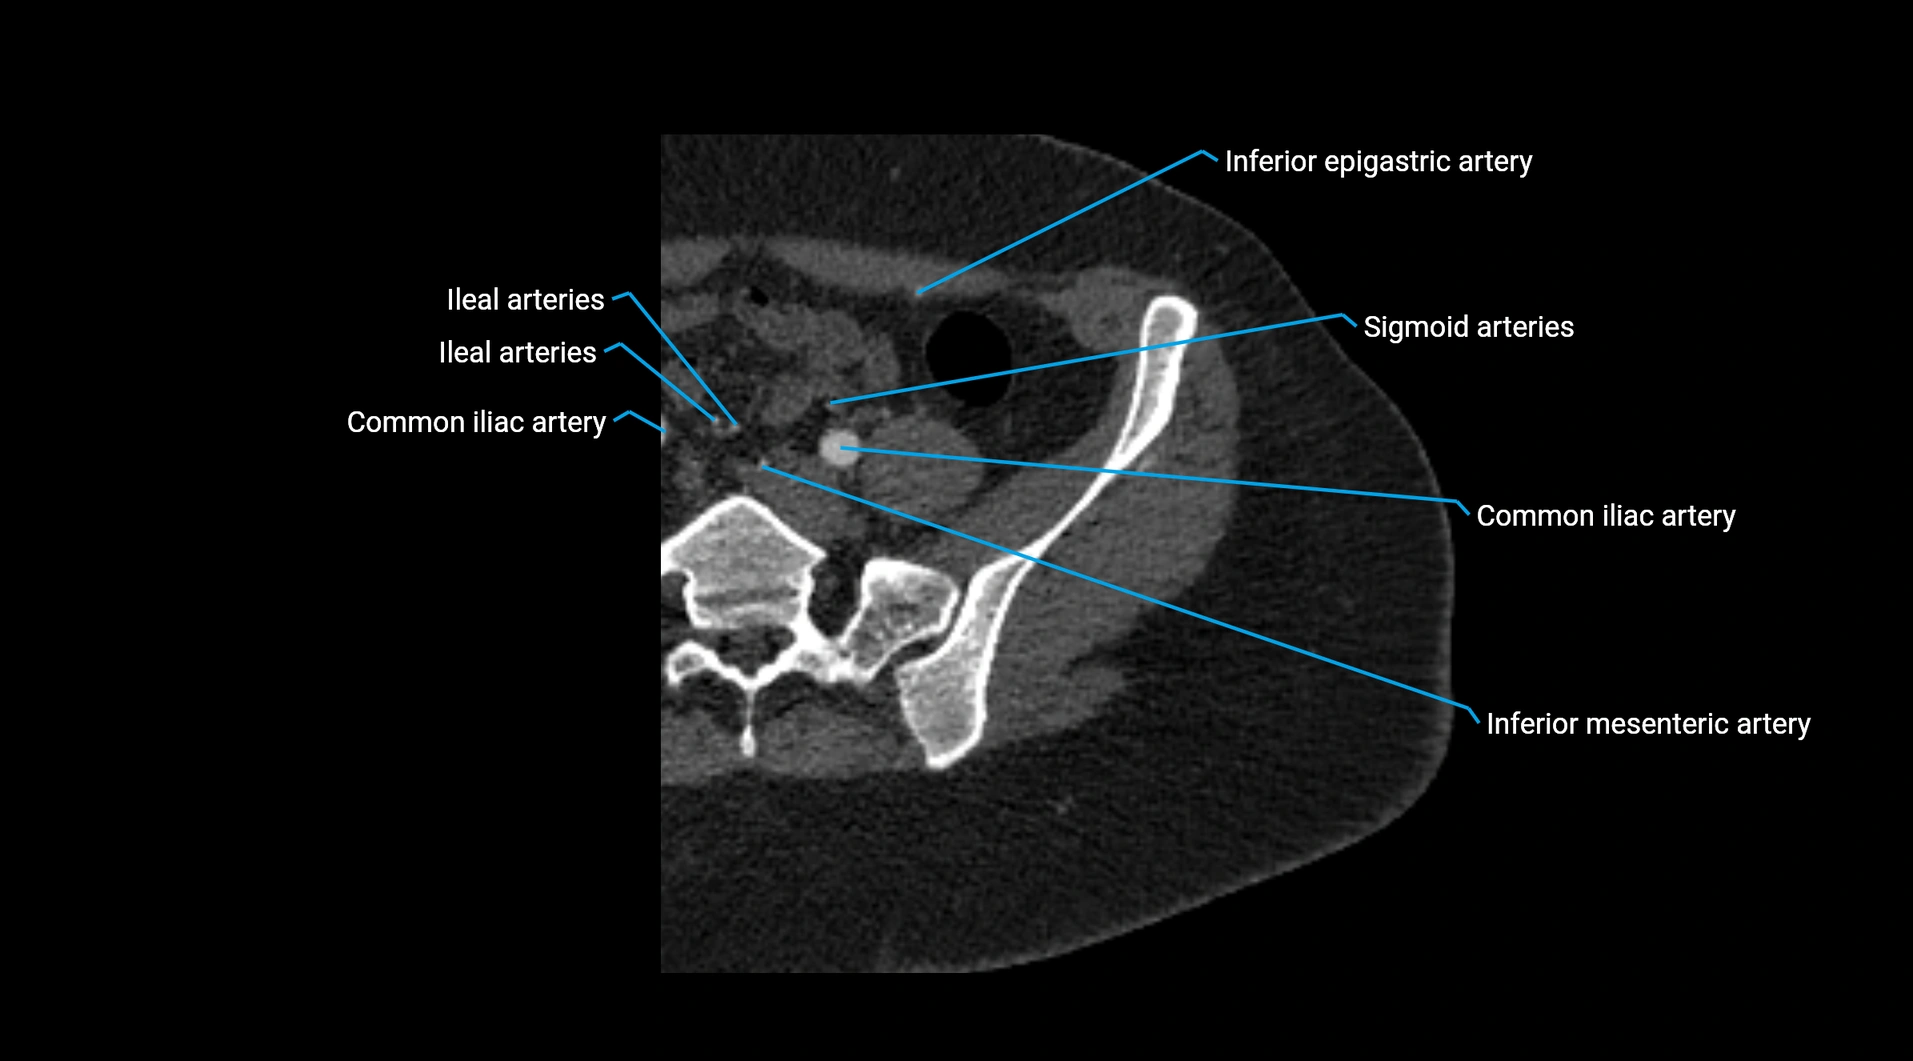

CT images

image

Contrast-enhanced CT (CTA):

• Gold standard for abdominal aortic imaging

• Provides excellent detail of lumen, wall, aneurysm, thrombus, and branch vessels

• Multiplanar and 3D reconstructions help in aneurysm measurement, stent graft planning, and dissection evaluation

• Unpaired visceral branches: celiac trunk, superior mesenteric artery (SMA), inferior mesenteric artery (IMA)

• Terminal branches: right and left common iliac arteries